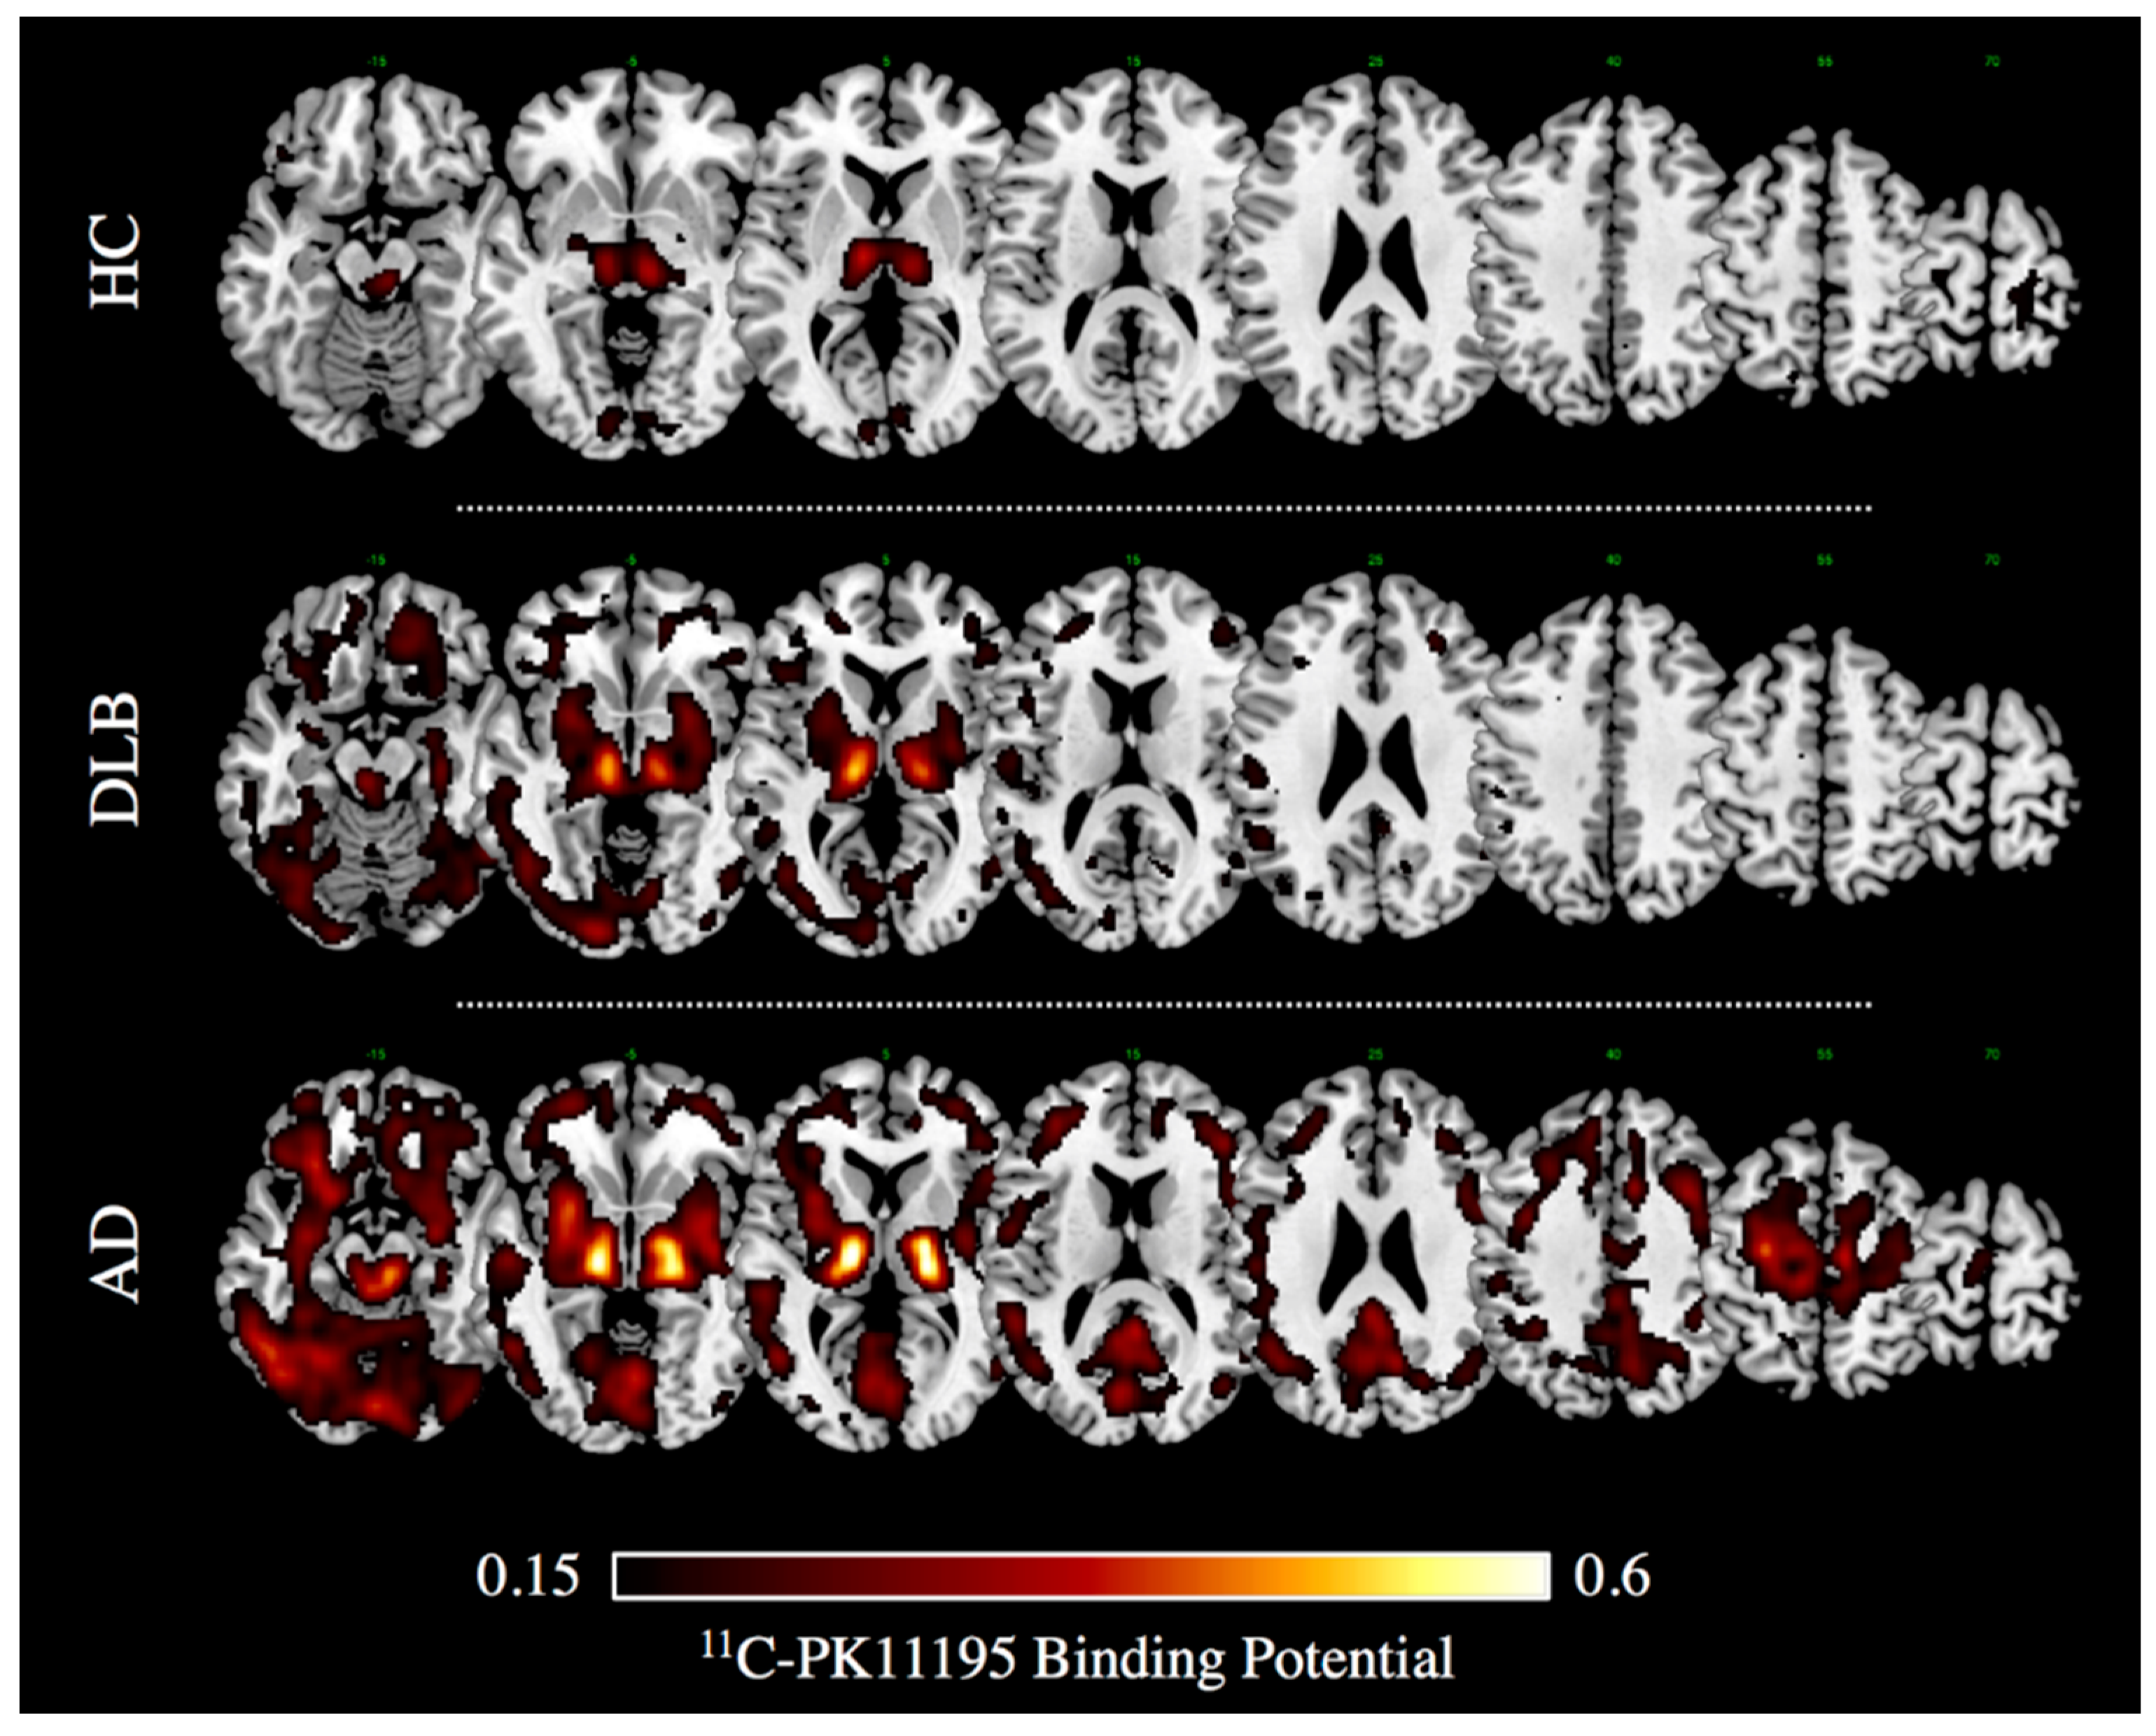

- Iannaccone, S.; Cerami, C.; Alessio, M.; Garibotto, V.; Panzacchi, A.; Olivieri, S.; Gelsomino, G.; Moresco, R.M.; Perani, D. In vivo microglia activation in very early dementia with Lewy bodies, comparison with Parkinson’s disease. Parkinsonism Relat. Disord. 2013, 19, 47–52. [Google Scholar] [CrossRef] [PubMed]